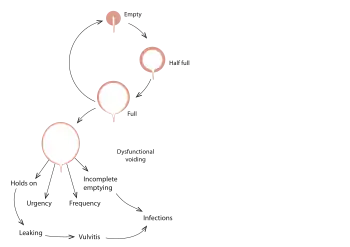

Urination, or voiding, is a complex activity. The bladder is a balloon-like muscle that lies in the lowest part of the abdomen. The bladder stores urine then releases it through the urethra, the canal that carries urine to the outside of the body. Controlling this activity involves nerves, muscles, the spinal cord and the brain.

The bladder is made of two types of muscles: the detrusor, a muscular sac that stores urine and squeezes to empty, and the sphincter, a circular group of muscles at the bottom or neck of the bladder that automatically stays contracted to hold the urine in and automatically relax when the detrusor contracts to let the urine into the urethra. A third group of muscles below the bladder (pelvic floor muscles) can contract to keep urine back.

A baby's bladder fills to a set point, then automatically contracts and empties. As the child gets older, the nervous system develops. The child's brain begins to get messages from the filling bladder and begins to send messages to the bladder to keep it from automatically emptying until the child decides it is the time and place to void.

Failures in this control mechanism result in incontinence. Reasons for this failure range from the simple to the complex.